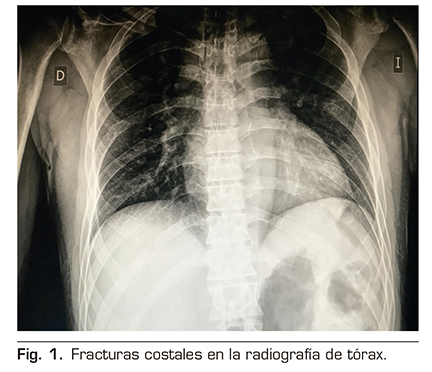

Figura 1

Figura 2

Figura 3